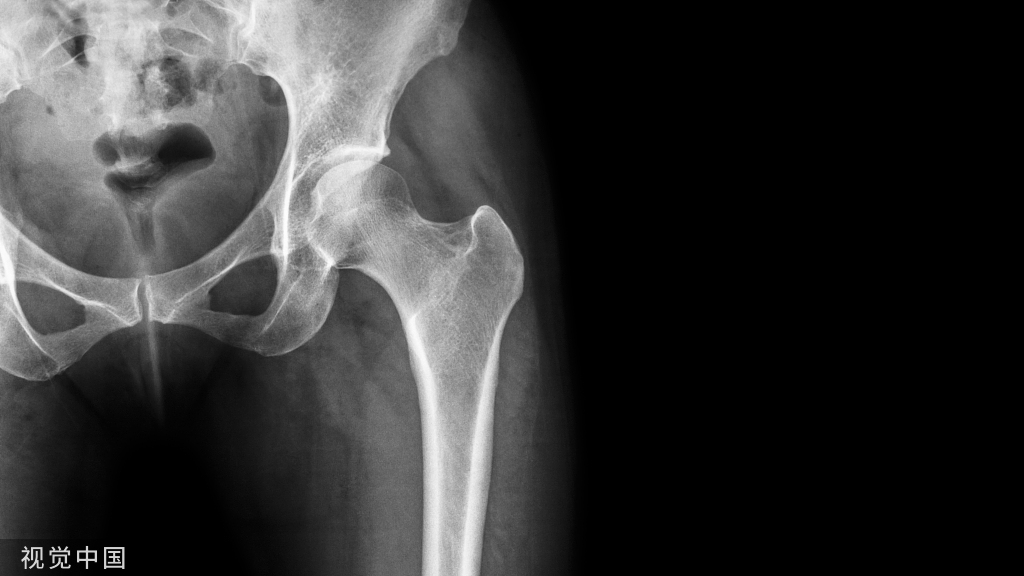

常规的膝关节周围截骨术主要包括胫骨高位截骨术(HTO)和股骨远端截骨术(DFO)。

图1 胫骨高位截骨术(HTO)